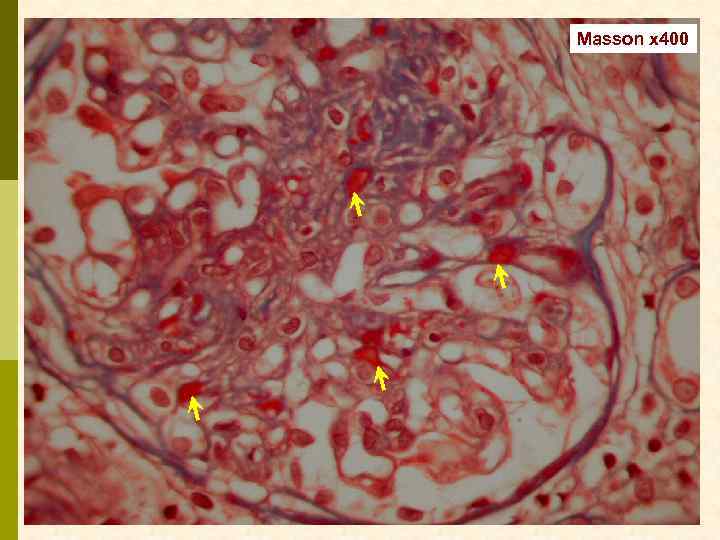

Masson x 400

Иммунофлюоресцентное исследование: p Клубочки: Ig. G (2+), Ig. M (3+), C 3 (2+), kappa (3+), lambda (1 -2+) - диффузная, субэндотелиальная и интракапиллярная, крупно-гранулярная экспрессия; p Стенки артериол: C 3 (2+); p Цилиндры: Ig. G (2+), Ig. A (3+), Ig. M (2+), C 3 (3+), kappa (3+), lambda (2+); p Реабсорбированные белковые капли: kappa (3+).

Предварительное гистологическое заключение: p Мембрано-пролиферативный, HCV-ассоциированный, криоглобулинемический(? ) гломерулонефрит с полным склерозом 47% клубочков, сегментарным склерозом 22% клубочков и формированием полулуний в 15% клубочков; p диффузно-очаговый выраженный острый канальцевый некроз; p выраженный артерио-артериолосклероз. Примечание: Криоглобулинемическая природа поражения будет уточняться при ЭМ-исследовании.

Заключение p Мембрано-пролиферативный гломерулонефрит, криоглобулинемический, ВИЧ-ассоциированный, на фоне гепатита С